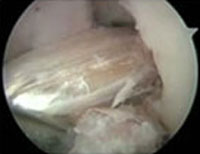

- The harvested replacement graft pulled into place through the holes which were just drilled and locked after flipping the Endo-CL Button.

- The new ligament is then held into place by two bio-absorbable screws or metallic screws.

Final Fixation